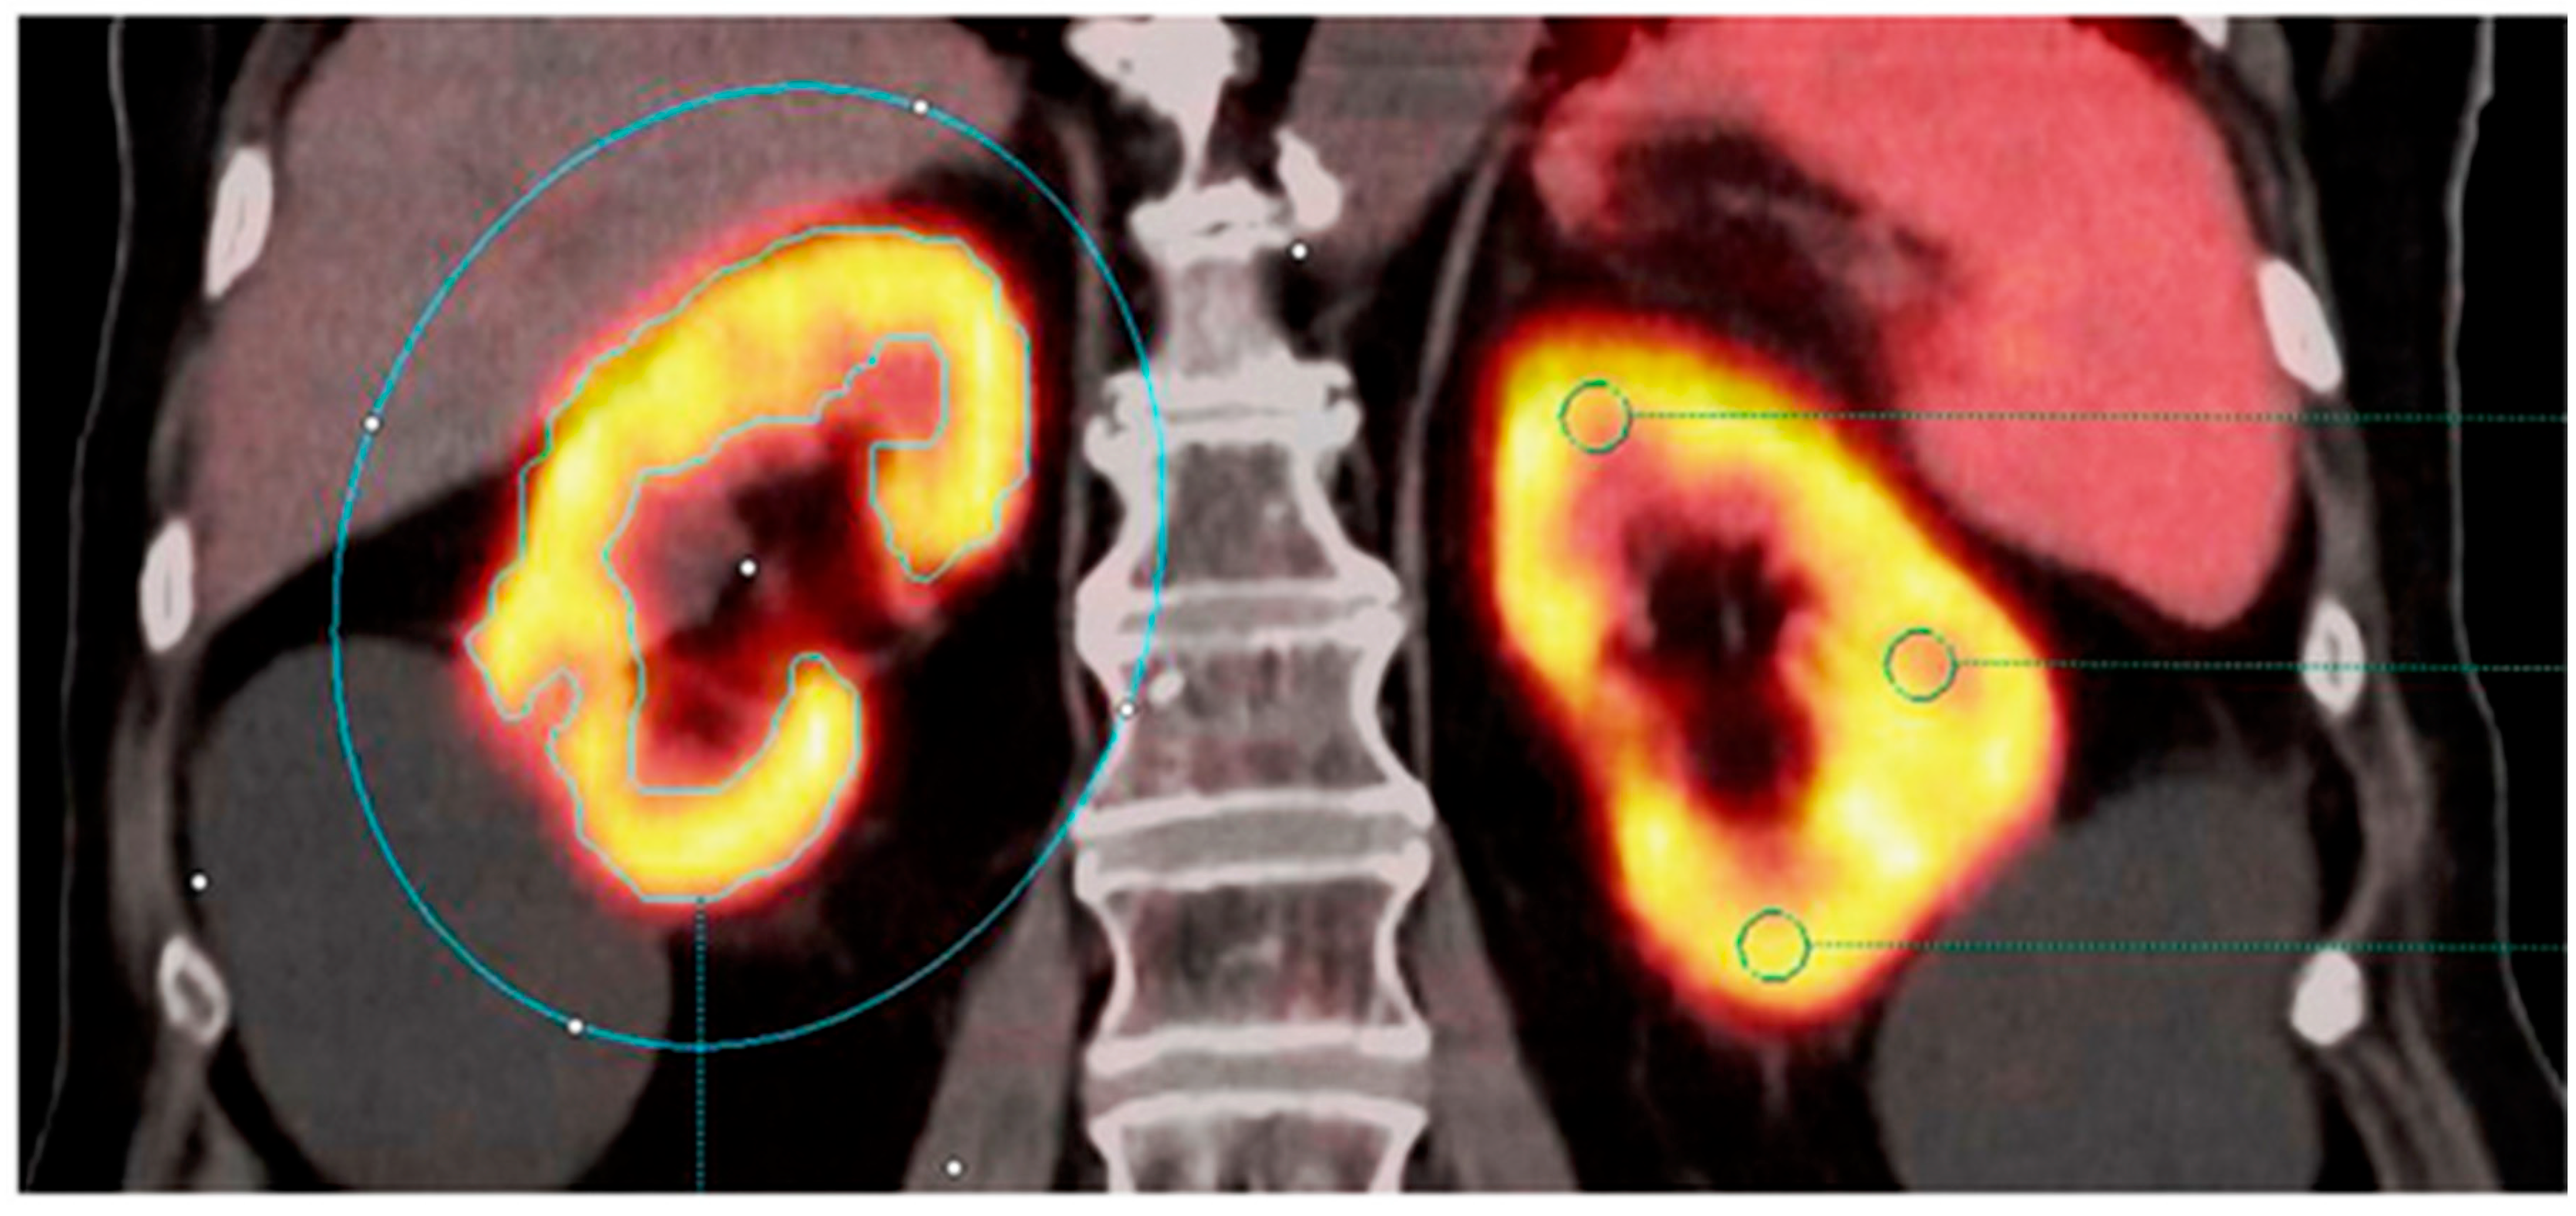

- Weissinger, M.; Seyfried, K.C.; Ursprung, S.; Castaneda-Vega, S.; Seith, F.; von Beschwitz, S.; Vogel, J.; Ghibes, P.; Nikolaou, K.; la Fougère, C.; et al. Non-Invasive Estimation of Split Renal Function from Routine 68Ga-SSR-PET/CT Scans. Front. Med. 2023, 10, 1169451. [Google Scholar] [CrossRef]

| Weissinger et al. [23] | 2023 | 6 | Germany | Original/Diagnostic Accuracy Retrospective | 25 | Reference standard tubular extraction rate (TER-MAG) from 99mTc-MAG3 scintigraphy and GFR CKD-EPI formula from serum creatinine. | 68Ga-ha DOTATATE |

| 68Ga-ha DOTATATE | Gallium-68 | Somatostatin receptor targeting | Moderate correlation of novel PET metrics with GFR; potential for split renal function assessment | Possible non-invasive GFR estimation from routine PET scans | Retrospective, indirect GFR references |